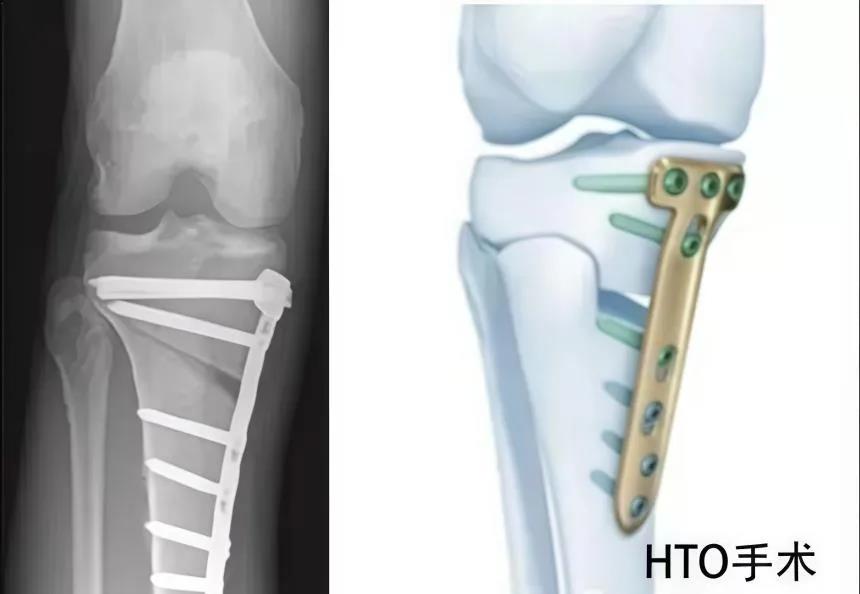

该科擅长对膝关节严重创伤(包括股骨远端骨折、髌骨骨折、胫骨平台骨折等)、膝骨关节炎阶梯化治疗、保膝治疗、膝关节微创单髁置换术、全膝关节置换术、膝关节翻修术具有丰富的临床诊疗经验,追求微创、无痛、快速康复。

对膝关节骨性关节炎采取阶梯化治疗方案,坚持中西并重、内外兼治的原则,取得满意的治疗效果。早期利用中医中药的传统优势,使用中医外治法,例如烫熨治疗、中药涂擦、雷火灸、中药塌渍等,同时辩证内服本院中药制剂及内服方药以及配合西药治疗,开展健康教育,运用运动疗法、物理治疗等辅助支持;中期开展软骨修复、截骨术、单髁置换术、髌股关节置换术等;对于终末期的膝关节OA采用全膝关节置换术。